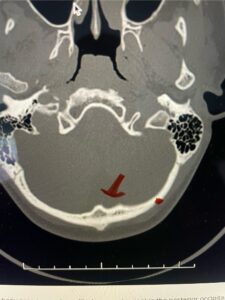

Fig. 2b: Axial CT scan of the brain demonstrating the thickness of the midline keel (red arrow) compared to the more lateral subocciput (red dot) making the keel ideal place for screw fixation